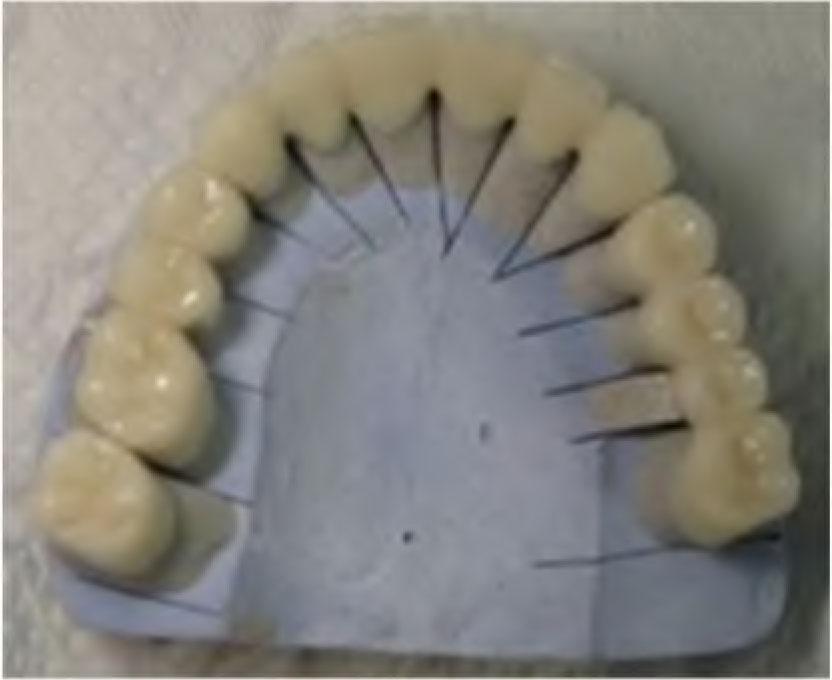

Then, the appropriate shade was selected using 3D-Master VITA guide (Vita Easyshade Compact, Vita Germany). Porcelain layering was made with porcelain VITA VM (9) (Vita Zahnfabric, Germany) (Figure 8 and 9).

6 units all-ceramic FDP (13–23), 4 units all-ceramic FDP (24–27), 3 units all-ceramic FDP (14–16) and 1 all-ceramic crown on 17 in the maxilla